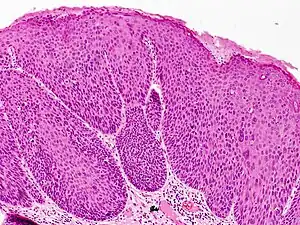

Bowenoid papulosis is a cutaneous condition characterized by the presence of pigmented verrucous papules on the body of the penis.[1]: 730 [2]: 408 They are associated with human papillomavirus, the causative agent of genital warts.[3] The lesions have a typical dysplastic histology and are generally considered benign, although a small percentage will develop malignant characteristics.

It is considered as a pre-malignant condition. Other terms used to describe the condition are: Erythroplasia of Queyrat, Squamous cell carcinoma in situ and Bowen's disease. The term bowenoid papulosis was coined in 1977 by Kopf and Bart and is named after dermatologist John Templeton Bowen.[4][5][6] The term "intraepithelial neoplasia" defines a premalignant intraepithelial change.